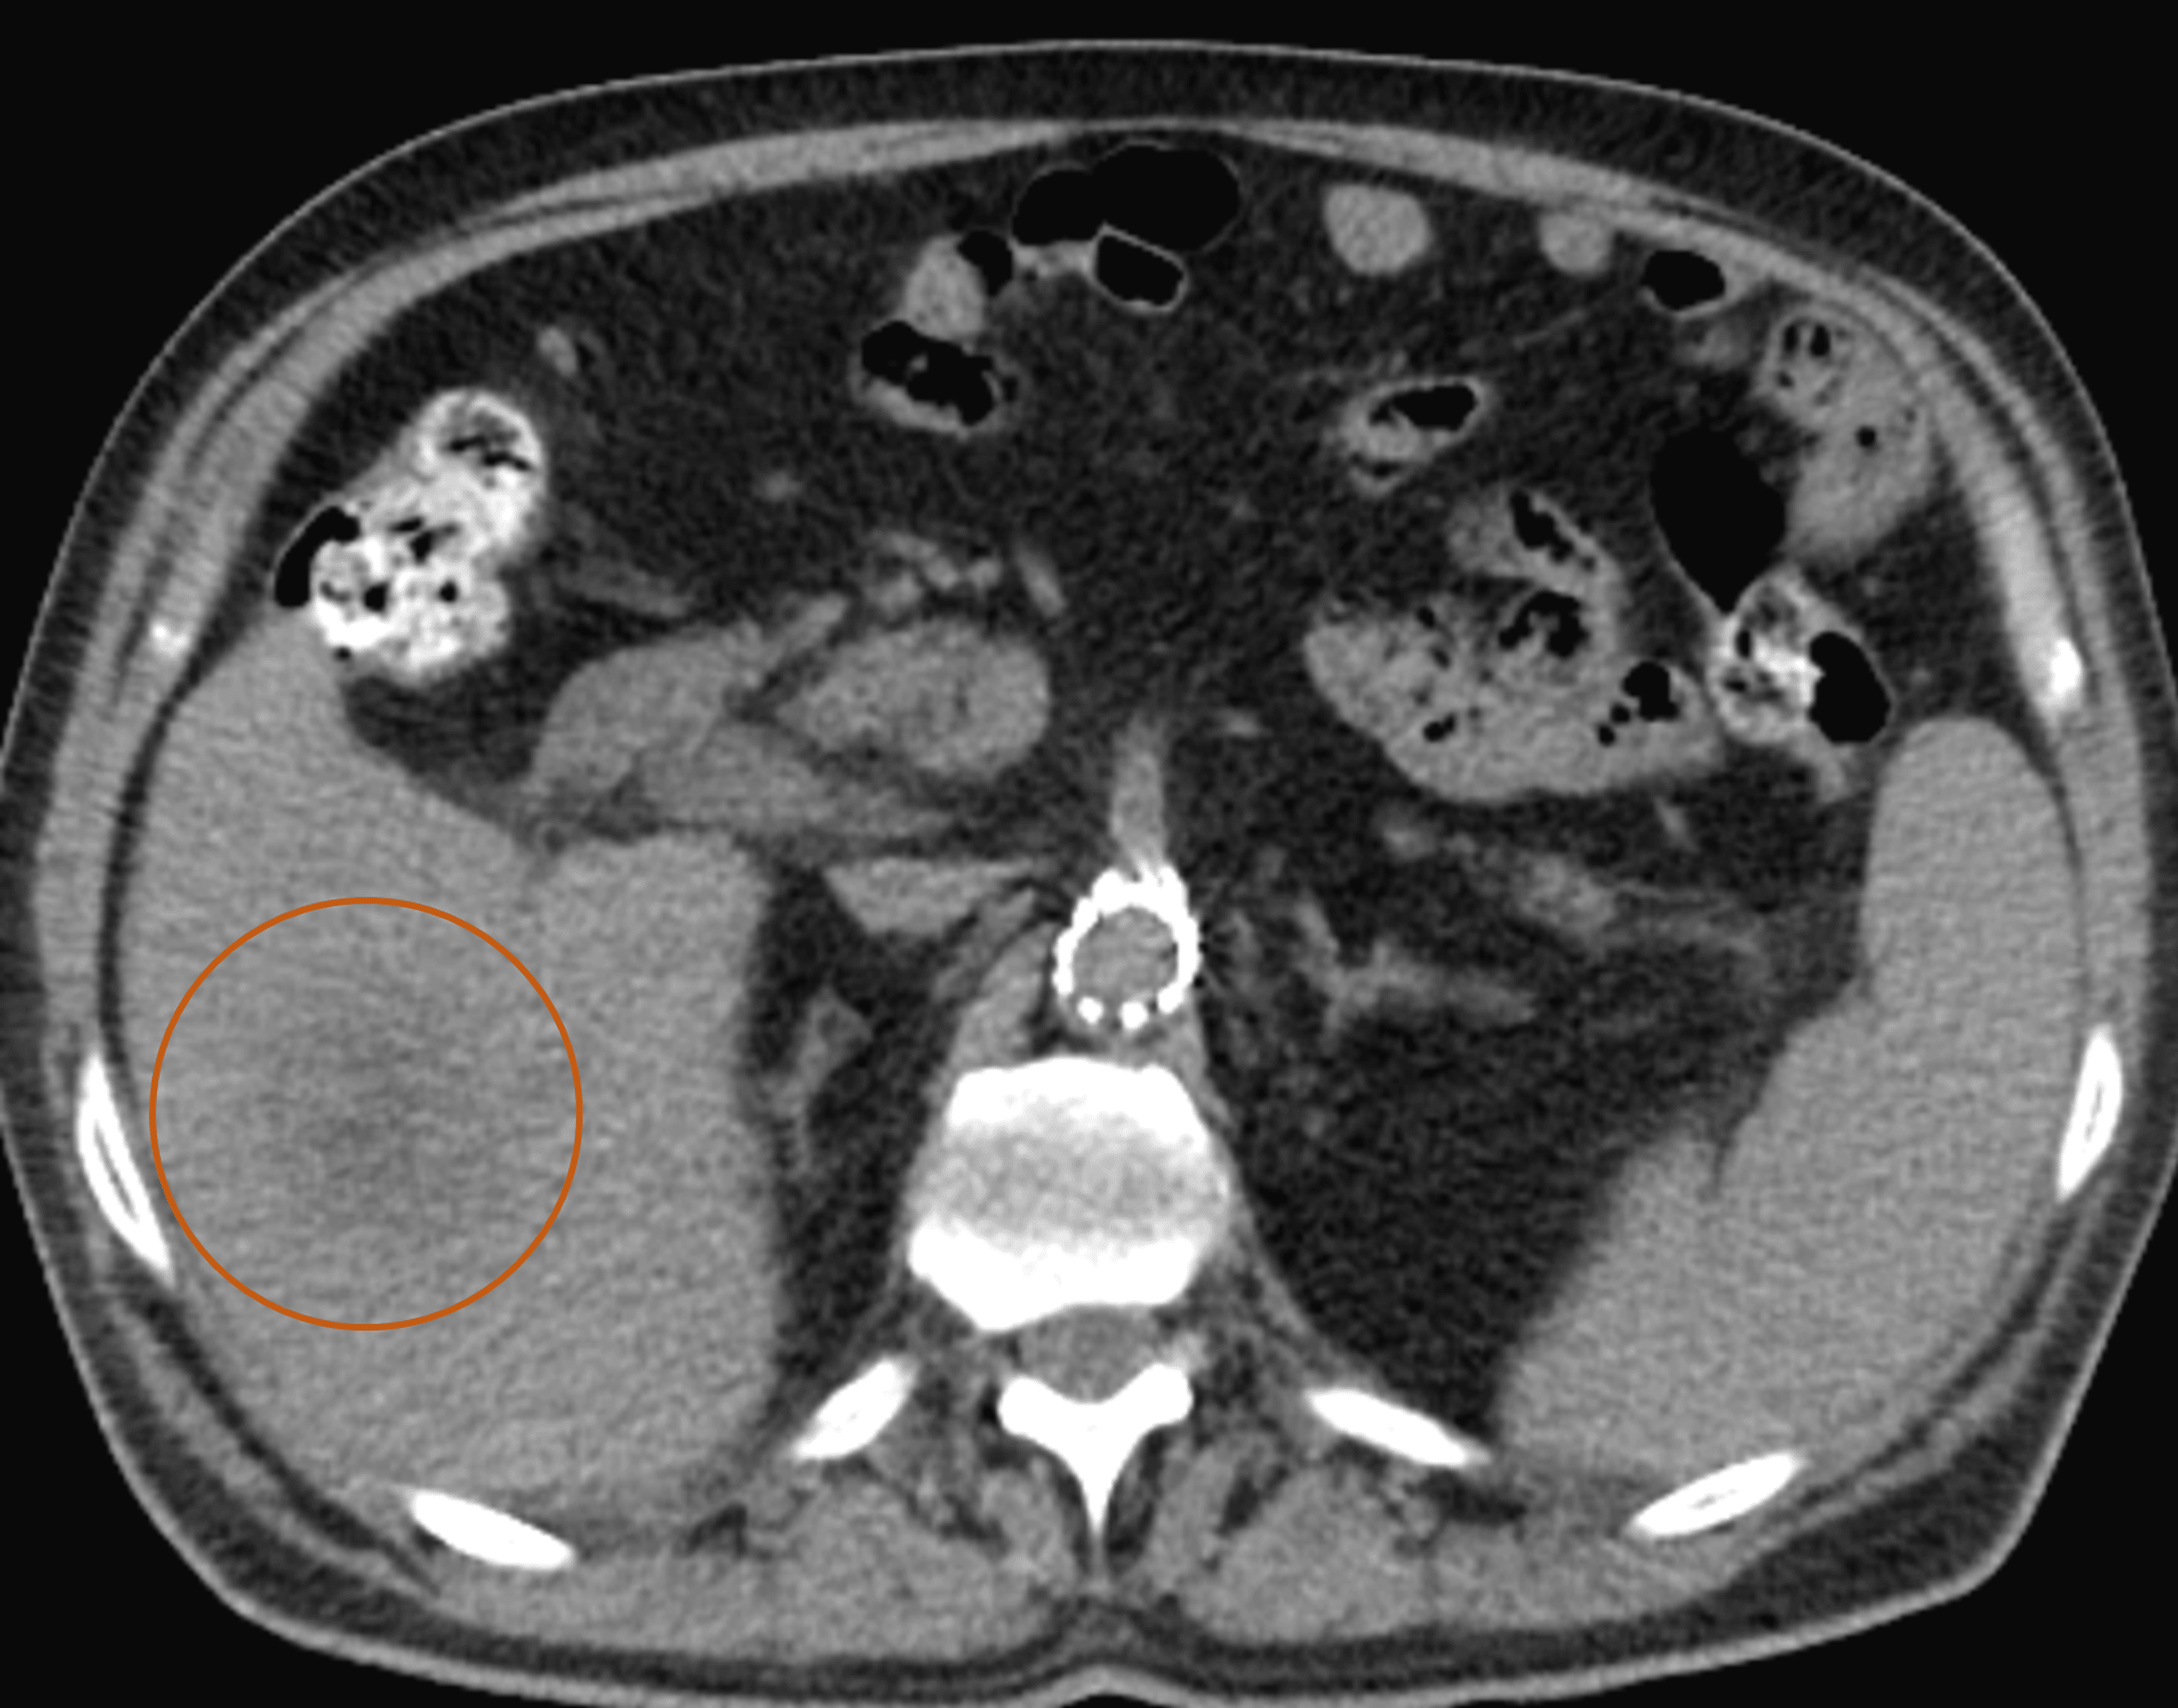

From www.researchgate.net

Liver abscess aspect on admission to hospital. Transverse abdominal CT Liver Abscess Wiki Pyogenic liver abscesses usually develops in the context of biliary disease, portal pyemia of various causes, through arterial. Liver abscess is a localized infection in the liver parenchyma that may be bacterial, fungal, or parasitic in origin. Associated with biliary tract obstruction (most common), cholangitis, diverticulitis, pancreatic abscess, appendicitis and inflammatory bowel disease. Liver Abscess Wiki.